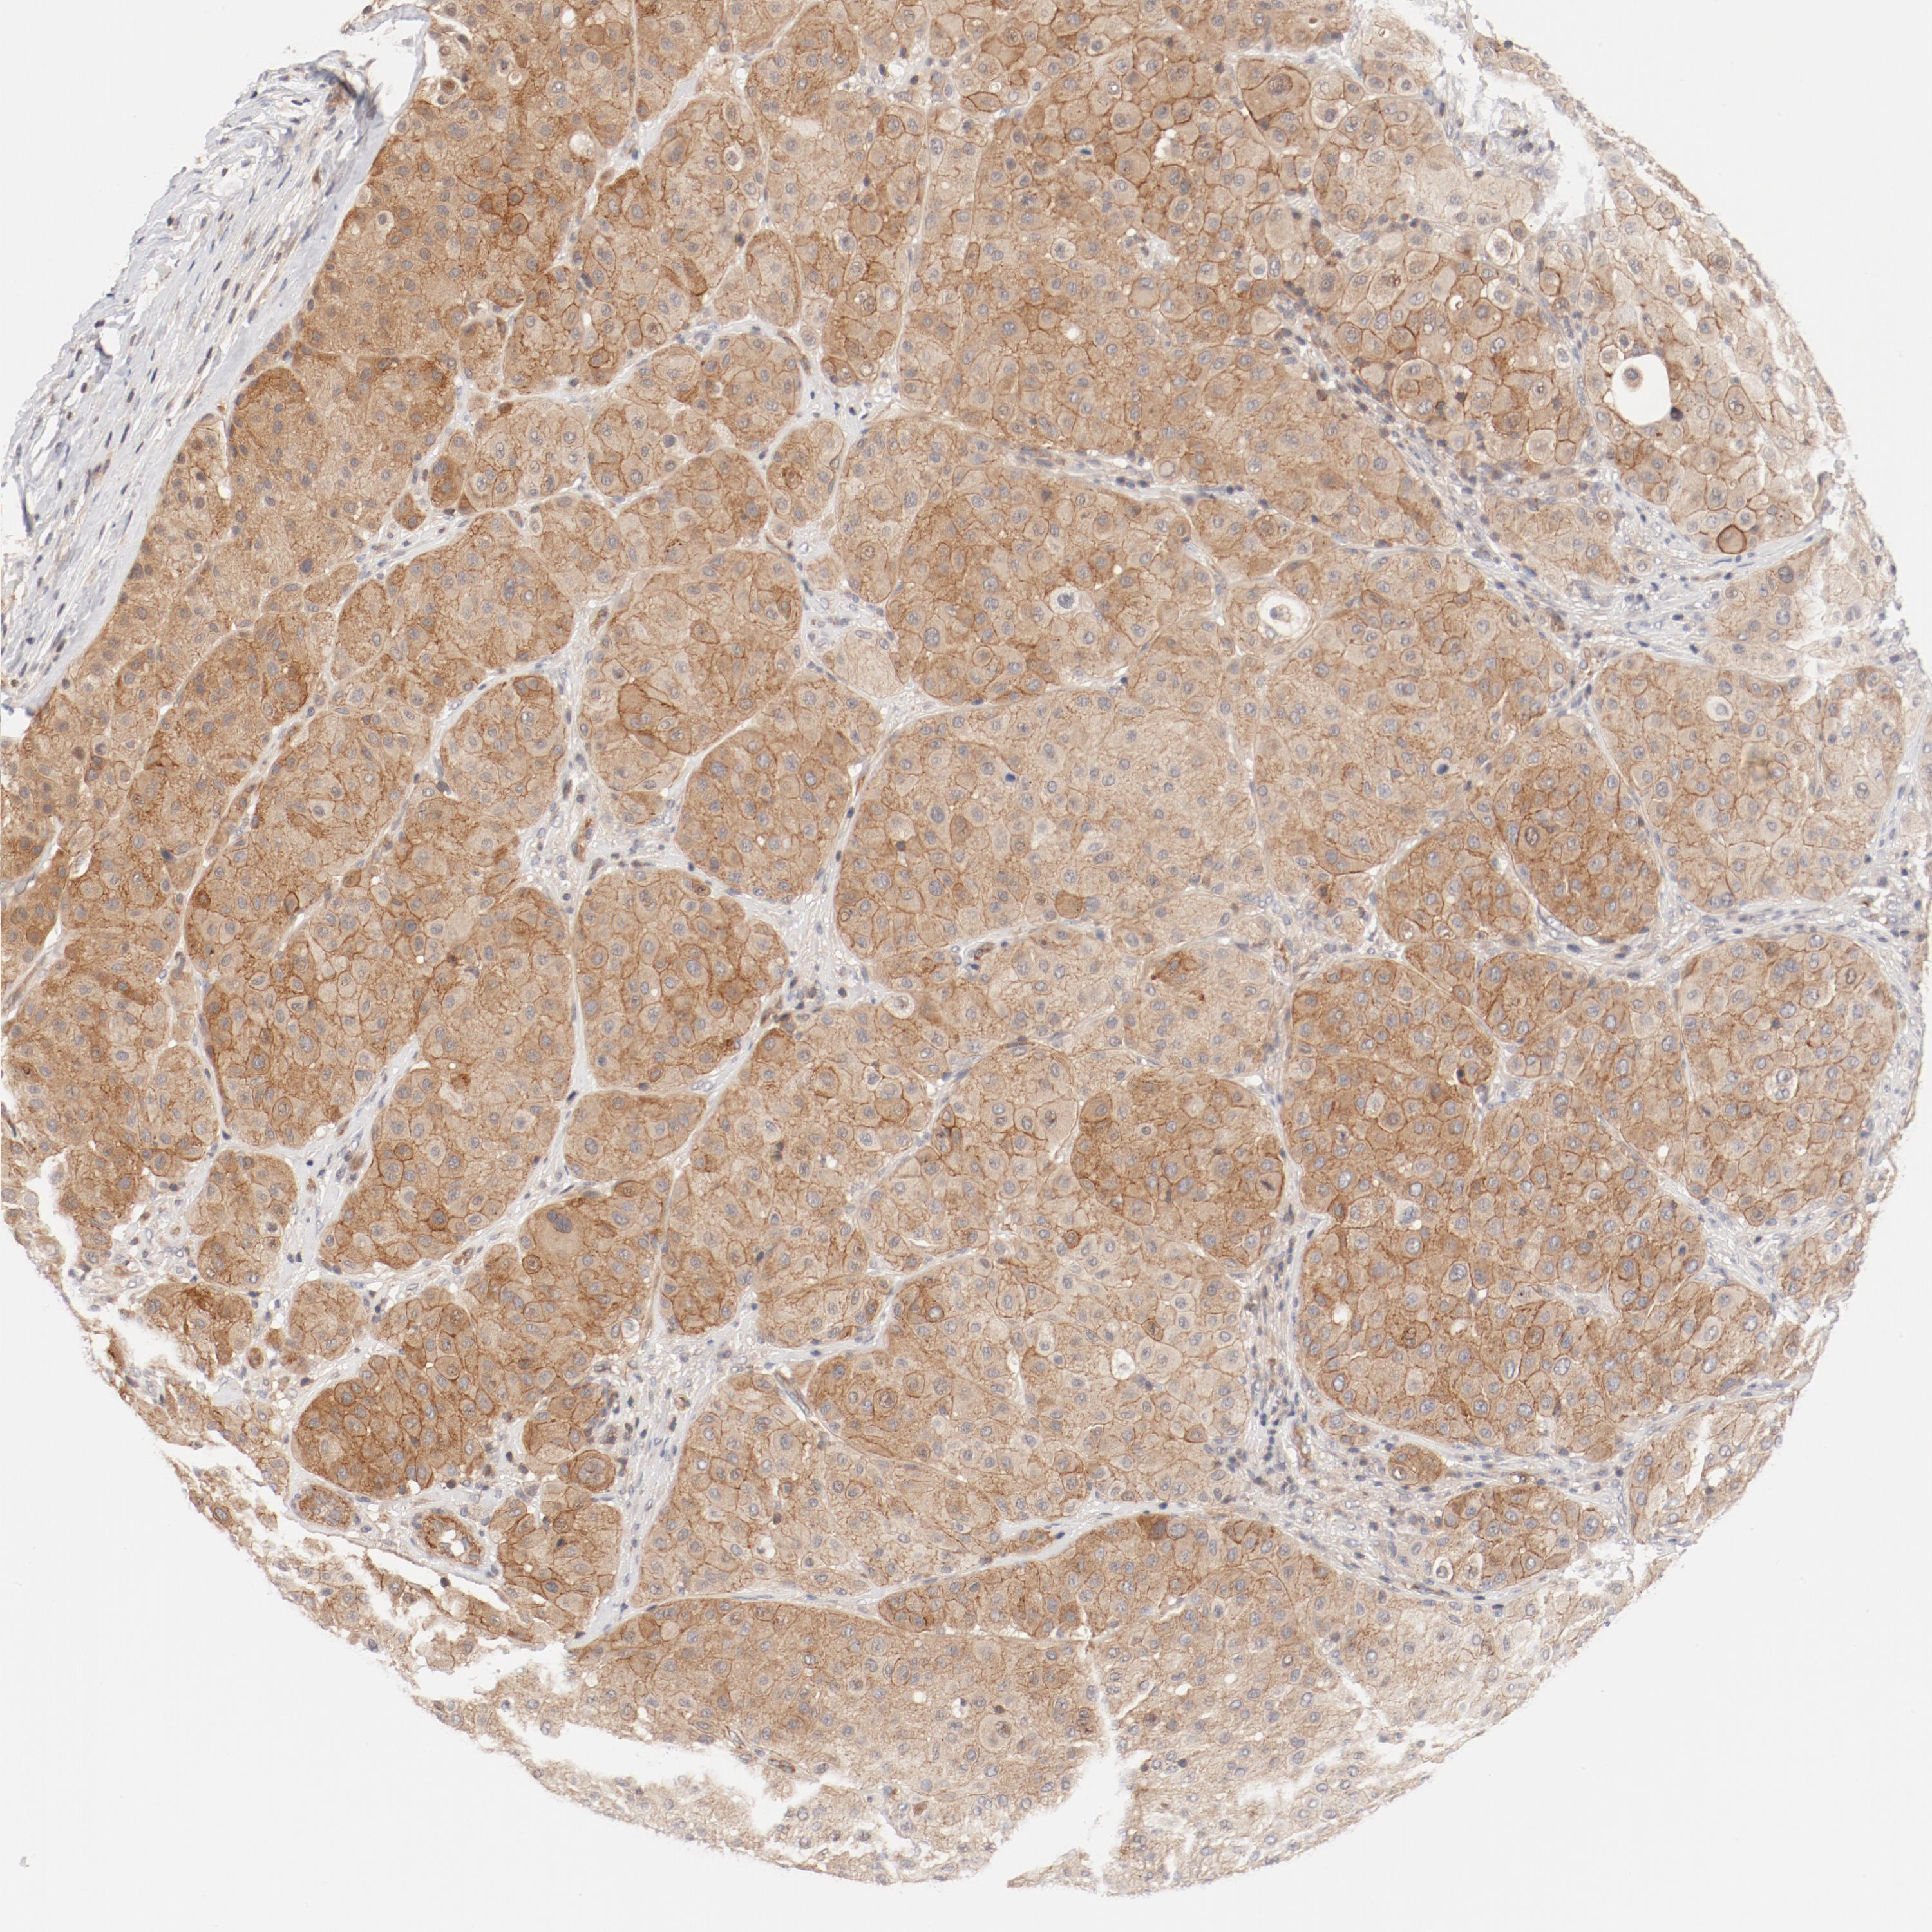

MELANOMA - Protein expressioni

A mouse-over function shows sample information and annotation data. Click on an image to view it in a full screen mode. Samples can be filtered based on level of antibody staining by selecting one or several of the following categories: high, medium, low and not detected. The assay and annotation is described here.

Note that samples used for immunohistochemistry by the Human Protein Atlas do not correspond to samples in the TCGA dataset.

Antibody stainingi

Antibody staining in the annotated cell types in the current human tissue is reported as not detected, low, medium, or high, based on conventional immunohistochemistry profiling in selected tissues. This score is based on the combination of the staining intensity and fraction of stained cells.

Each image is clickable and will lead to virtual microscopy that enables deeper exploration of all samples and also displays staining intensity scores, fraction scores and subcellular localization as well as patient and tissue information for each sample.

Antibody HPA003866

Staining

High

Medium

Low

Not detected

Intensity

Strong

Moderate

Weak

Negative

Quantity

>75%

75%-25%

<25%

None

Location

Nuclear

Cytoplasmic/membranous

Cytoplasmic/membranous,nuclear

Malignant melanoma, NOS

Malignant melanoma, Metastatic site